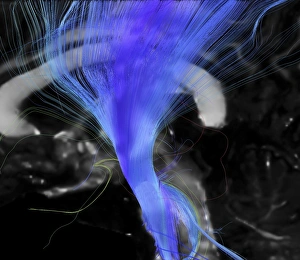

The central nervous system, the intricate network that governs our every thought and movement, is a marvel of complexity. From the delicate cerebellum tissue to the detailed light micrograph capturing its essence, we are reminded of its importance in maintaining balance and coordination. Anatomy comes alive as we explore the human brain from an inferior view. The intricacy of brain fibers is revealed through DTI MRI scans like C017/7099 and C017/7035, showcasing their vital role in transmitting information throughout this extraordinary organ. Artistic renderings bring us closer to understanding the medulla oblongata's significance within the brain. Its portrayal in various artworks allows us to appreciate how it controls essential functions such as breathing and heart rate. As we delve deeper into studying the central nervous system, models of the human brain provide invaluable insights into its structure and organization. Lateral views reveal countless regions responsible for cognition, emotion regulation, sensory perception, and motor control. Microscope slides offer glimpses into nerve cells' intricate architecture—a testament to their ability to transmit electrical signals at lightning speed. Meanwhile, glial stem cell cultures captured under a light microscope remind us of their crucial role in supporting neuronal function. Finally, artistic representations unveil the limbic system's enigmatic nature—an interconnected web responsible for emotions and memory formation. These captivating artworks allow us to visualize this complex network within our brains. Exploring these hints provides a glimpse into the awe-inspiring world of our central nervous system—the very foundation upon which our thoughts, actions, memories reside—reminding us just how remarkable our brains truly are.